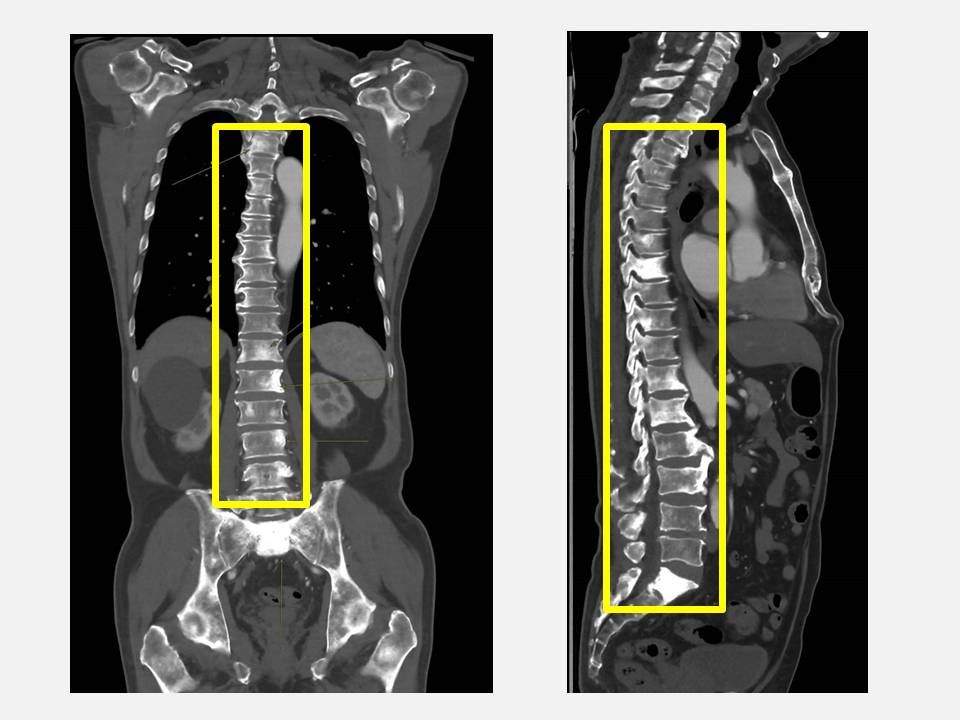

大里仁愛醫院泌尿科主任劉緯陽表示,攝護腺癌為台灣男性常見癌症,由於早期症狀不顯著,許多患者常誤以為是排尿功能退化,或是直到出現骨痛才求診,此時往往已進入晚期,余先生的病例顯示,雖然背痛是常見的老化現象,但在臨床上也是攝護腺癌轉移的警訊之一,若非透過健檢及時發現並展開治療,一旦病程持續惡化,恐引發骨折或神經壓迫等嚴重併發症。

針對攝護腺癌骨轉移的治療,劉緯陽主任指出,目前針對骨轉移多以荷爾蒙療法為首選,抑制男性荷爾蒙以延緩癌細胞生長,並搭配新一代標靶藥物或化療,針對骨轉移導致的疼痛,院方則會給予骨保護治療或放射治療,在控制病情的同時,也致力於維持患者的生活品質與存活期。